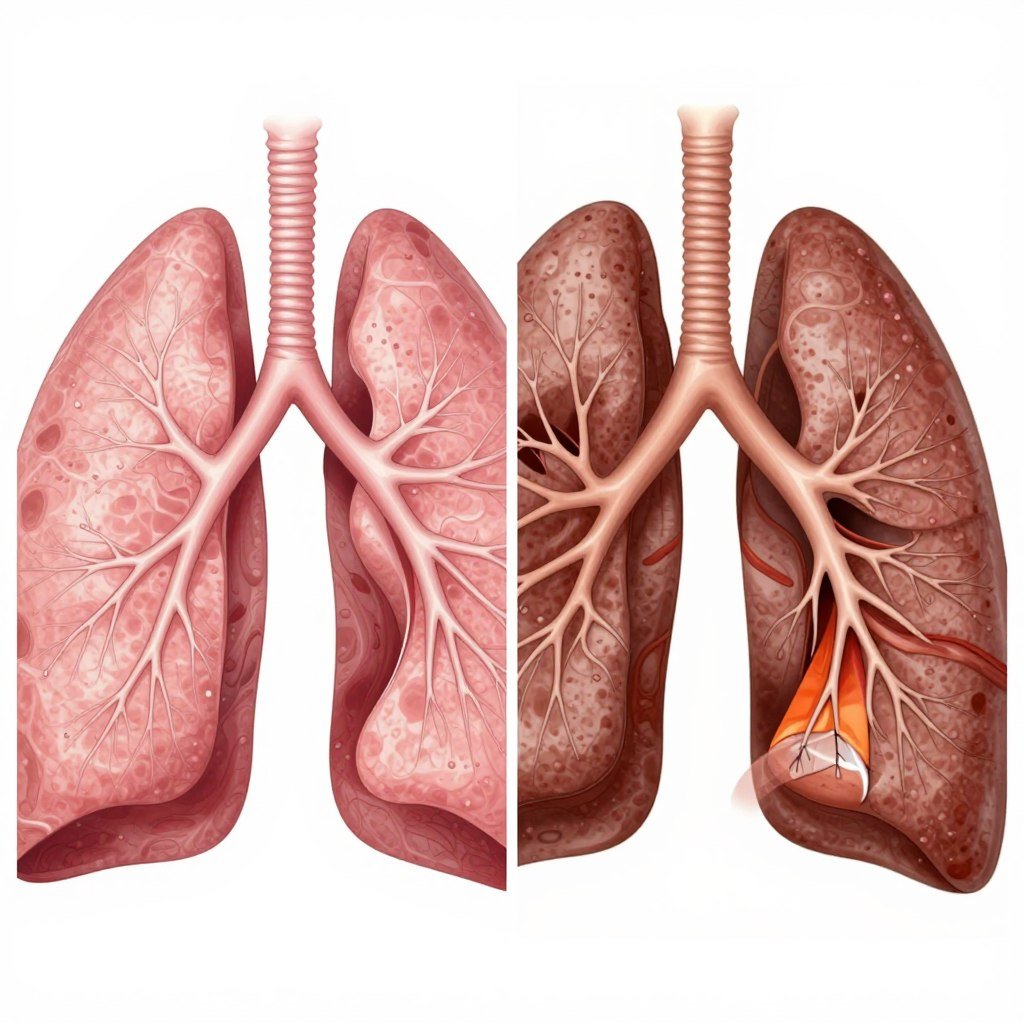

Two primary conditions fall under the COPD umbrella. These include emphysema chronic bronchitis, which often occur together in people with COPD.

Understanding the Two Main Types

Chronic bronchitis involves inflammation of the airways. The bronchial tubes become swollen and produce excess mucus that blocks air passages.

Emphysema affects the air sacs in the lungs. These tiny structures, called alveoli, become damaged and lose their elasticity over time.

Most people copd experience both conditions simultaneously. The combination creates the characteristic breathing difficulties associated with this obstructive pulmonary disease.

In healthy lungs, air flows freely through airways into air sacs. These delicate structures facilitate oxygen exchange with the bloodstream.

COPD damages this intricate system. Airways become inflamed and narrowed while air sacs lose their ability to expand and contract properly.

The result is trapped air in the lungs. This phenomenon makes it increasingly difficult to breathe out completely.

COPD is a chronic, progressive condition. The lung damage characteristic of emphysema chronic bronchitis cannot be completely reversed.

Permanent structural changes occur in airways and air sacs. Once these delicate structures are damaged, they cannot regenerate to normal function.

This differs fundamentally from reversible conditions like asthma. While asthma involves temporary airway narrowing, COPD causes permanent tissue damage.